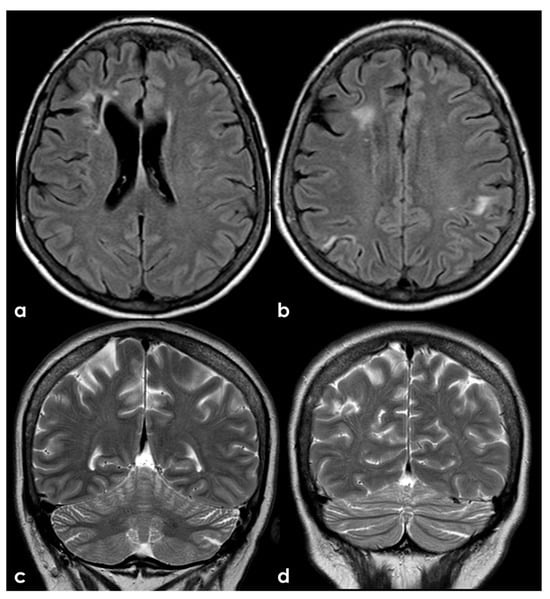

Figure 5.

An example of multifocal cerebellar ischemic lesions in a patient with APS (double positivity). Brain MRI (axial FLAIR in (a,b), coronal T2W sequence in (c) shows the poromalacic evolution of multiple ischemic lesions involving both cerebellar hemispheres (right ≥ left). No causes other than APS were identified in this patients.